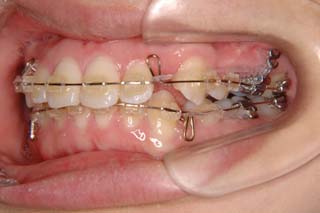

最終仕上げの段階です。かなり太めのワイヤーが入っていますが、このワイヤーの後にオーバーコレクション(元々の歯の捻れが有った場合、後戻りで出てきやすいので、わざと過剰に捻れを治しておく事)を行うための、細めのワイヤーを使う事もあります。

上顎前歯、下顎前歯の前突が見られます。大きな叢生は見られませんが、上下の口唇前突感も伴います。このような不正咬合を上下顎前突と言います。審美的な事もさることながら、歯軸の傾斜の問題から歯にかかるベクトルが良くない事、口唇の筋肉の緊張を強いるような不調和を示す事などから、不正咬合の一つとして考えられています。上顎前突傾向も伴っていますので、積極的に上顎前歯の後退を行う目的で、上顎に固定源となる 目的外使用の オーソアンカー SMAPシステム を装着しました。現在では、歯科矯正用アンカースクリュー(デュアルトップオートスクリュー、ISAアドバンスなど)といった、医療機器認証番号がある製品を用いることが多くなりました。

使用した主な装置名:TPB、マルチブラケット装置、オーソアンカー SMAPシステム